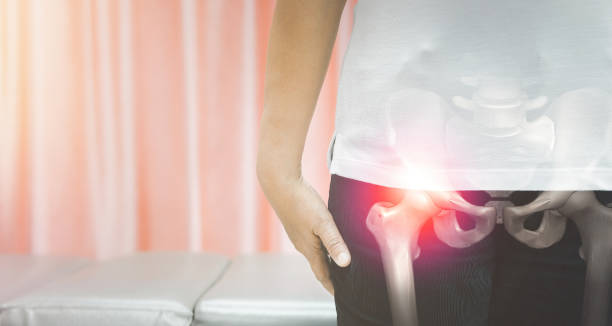

고관절 수술 후 회복에 필요한 시간을 알려드려요. 고관절 수술은 고관절의 변화로 인한 통증 및 기능 장애를 개선하기 위해 수술적인 처리를 하고, 수술 후 환자들은 회복 기간을 거치게 됩니다.

이 글에서는 고관절 수술 후 회복 기간과 주의사항에 대해 알려드리도록 하겠습니다.